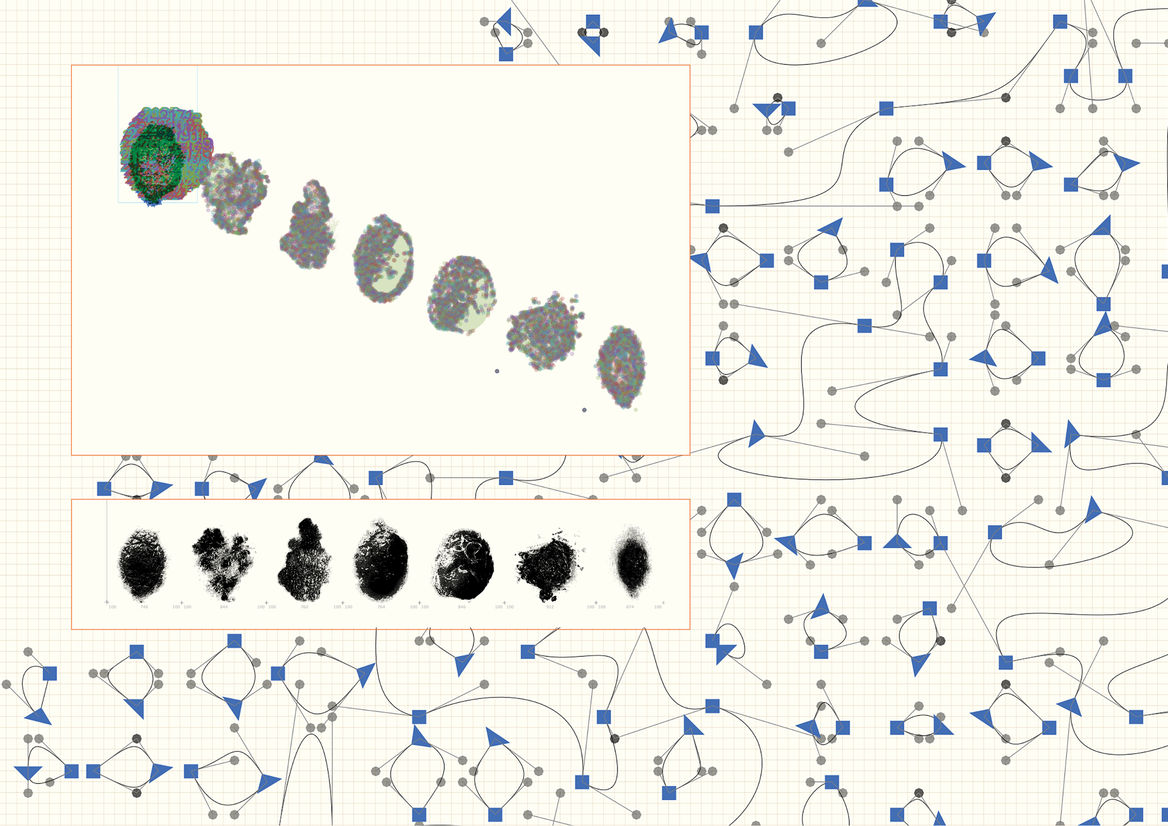

We created a usable font, made up of seven glyphs of a single character - the full stop. Each glyph was designed in partnership with New Zealand medical professionals to accurately represent one of the visual symptoms of Melanoma. When viewed at a small size, the glyphs all look like slightly misshapen full stops. But as point size increased, more and more detail is revealed in each character, until the true nature of each spot is impossible to ignore.